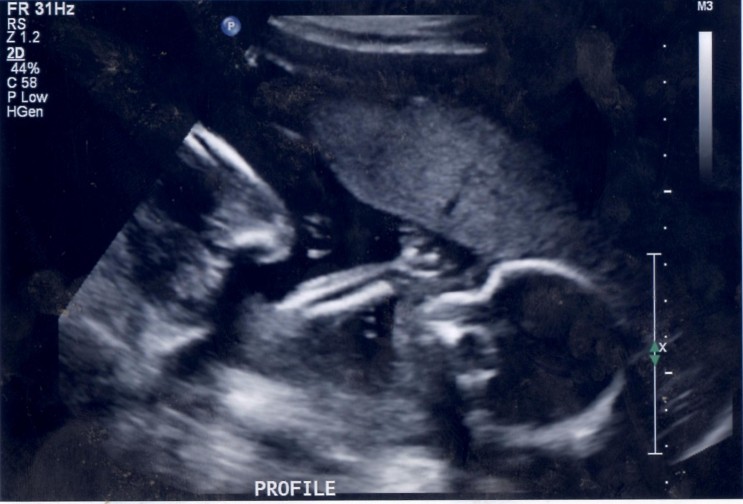

Can tell from these pics? Wrong area. Need a potty shot.

Looks like you will be having a thumb sucker

baby looks cute, but no gender clues here, sorry!